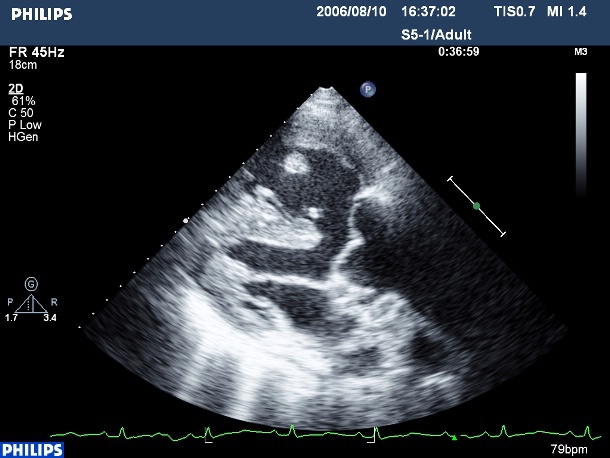

我用上面的圖來說明一下為什麼會發紺好了...。右心室裝的是身上用過、含氧量很低的血液,正常情況下是要經過右心室出口、肺動脈瓣、肺動脈、然後把這些缺氧血送去兩邊的肺部換成充滿氧氣的血液,再送回給心臟供全身使用的。

然而法洛氏四重症患者的右心室出口因為有明顯狹窄,血液送去肺動脈就會有很高的阻力,因此有一部分的缺氧血就順勢從心室中膈缺損溜走,跑進左心室和充氧血攪和在一起。左心室裡面的血就變得含氧純度降低,因此送到全身的血液也就有點"缺氧"了。同理可知,當右心室出口越窄、肺動脈瓣越小、或是肺動脈血管發育越差時,從心室中膈缺損溜走的缺氧血就越多,病童發紺的程度就越明顯。